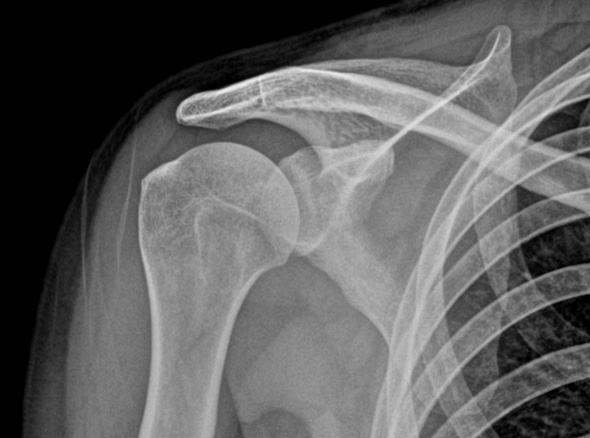

오십견은 어깨를 감싸고 있는 관절 조직인 관절낭에 염증이 발생하면서

유착되어 어깨의 움직임이 제한되고 통증이 유발되는 질환입니다.

가벼운 외상이나 혹은 회전근개 질환 등

여러가지 어깨 질환이 동반되어 나타나게 됩니다.